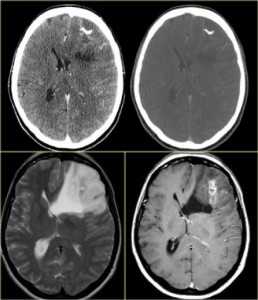

КТ и МРТ головного мозга. Аксиальные КТ до и после контрастировали, сагиттальная МРТ с контрастировавшем, аксиальная Т2-взвешенная МРТ головного мозга. Герминома (КТ и МРТ)- опухоль области шишковидной железы